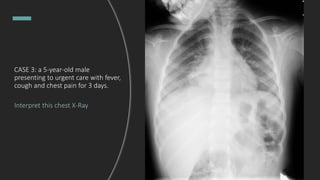

CASE 3: a 5-year-old male

presenting to urgent care with fever,

cough and chest pain for 3 days.

Interpret this chest X-Ray

Right lower lobe pneumonia!

The patient is given

Amoxicillin - Clavulanate and

discharged home. But then...